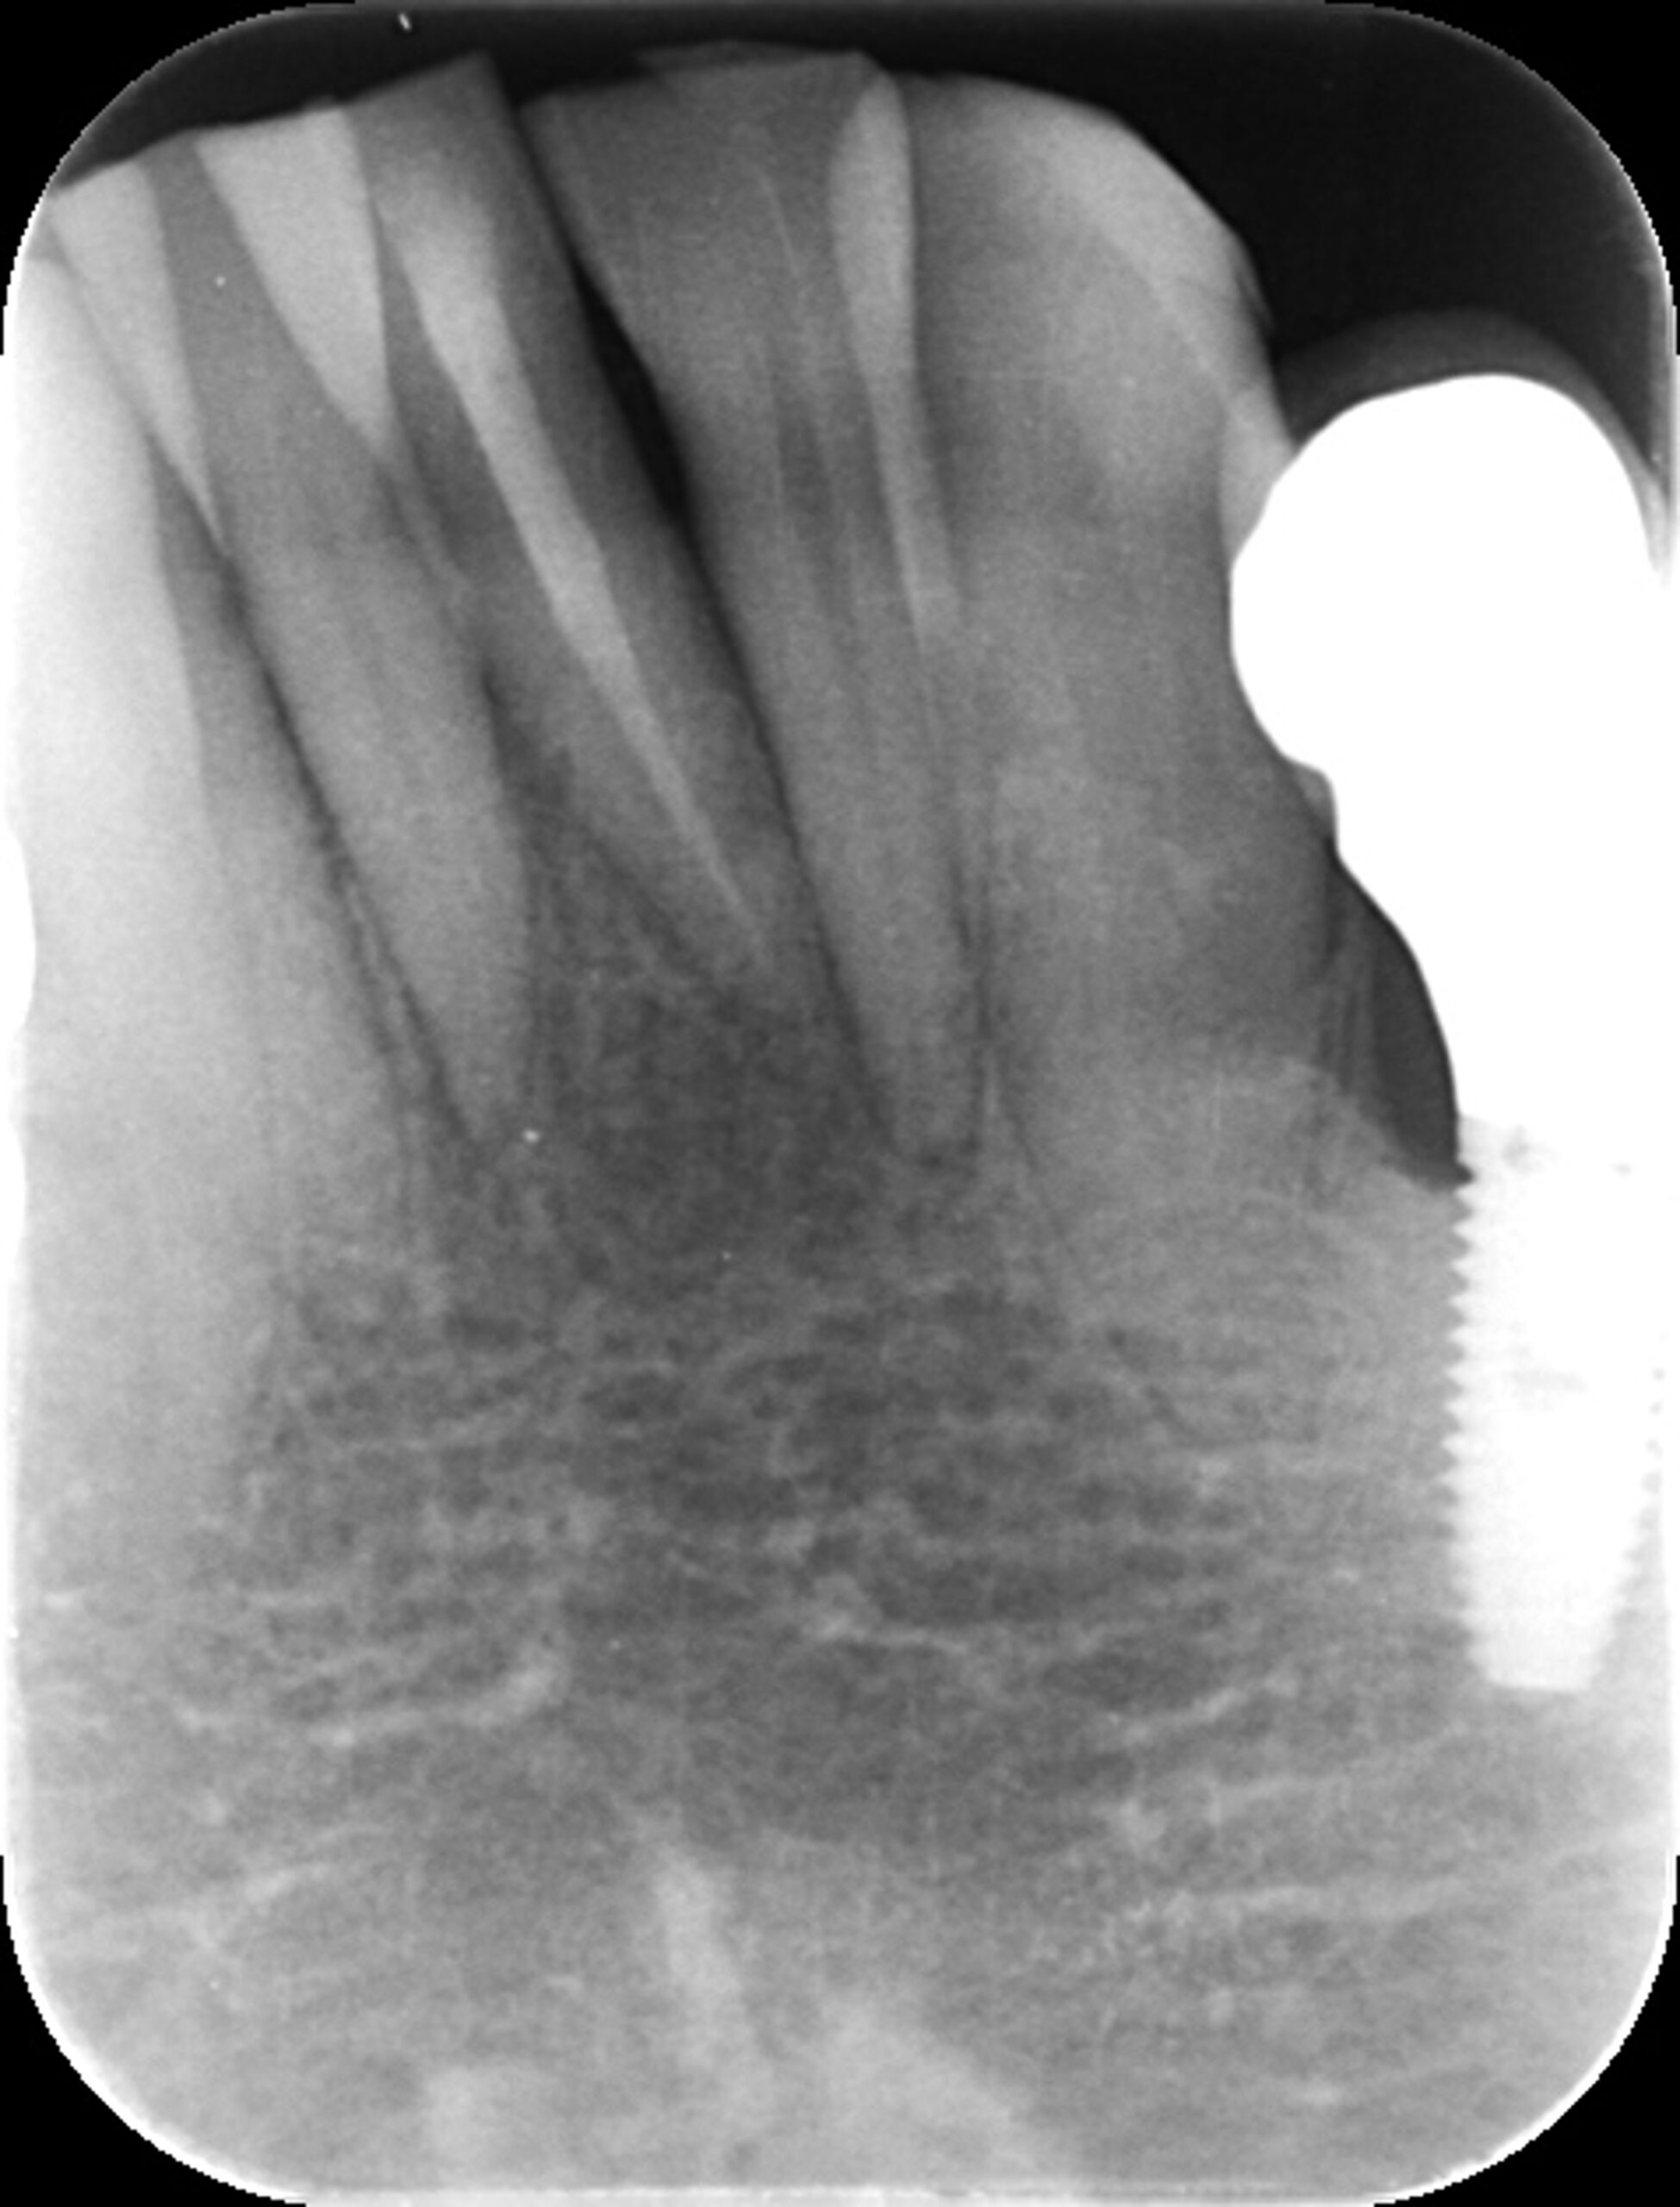

症例4

治療経過

①![]() 術前 |

②![]() 根管治療後3か月経過 |

③![]() 根管治療後1年経過時 |

④![]() 根管治療後2年経過時 |

神経の治療後、①→②→③→④と時間をかけて徐々に治ってくることがあります。

神経の治療は細菌感染を除去する治療です。細菌がいなくなれば、無駄に神経をとらなくても良い歯もあるかもしれません。

| 項目 | 詳細 |

|---|---|

| 患者様データ | 30代 男性 |

| 来院時の主訴 | 「他院で右上の歯3本とも神経をとる必要があると言われた。なんとか神経を残したい。」 |

| 術前検査結果 |

右上第一小臼歯:打診痛(+)・歯髄の生活反応有り 右上第二小臼歯:打診痛(+)・歯髄の生活反応無し 右上第二大臼歯:打診痛(ー)・歯髄の生活反応有り |

| 医院の診断 |

右上第一小臼歯:健全→術前に神経が残せる可能性のある歯と診断 右上第二小臼歯:慢性根尖性歯周炎→術前に神経が残せない歯と診断 右上第二大臼歯:無症候性可逆性歯髄炎→術前に神経が残せる可能性のある歯と診断し、術中に神経を残せると診断 |

| 通院期間 | 2年半 |

| 来院回数 | 10回(定期的なチェック含む) |

| 治療費 | 350,000円(税抜) 《内訳》 右上第二小臼歯:精密根管治療70,000円、ファイバーポストコア20,000円、セラミック治療120,000円 右上第二大臼歯:歯髄温存療法55,000円、セラミック治療85,000円 |

| リスクと副作用 | ①根管治療歯は長期的には破折するリスク ②メインテナンスが必要 |

| ココがこだわりのポイント☝ |

レントゲン検査や患者様の訴える症状だけでは神経を残せるかどうかは断定できません。 この方もレントゲン写真上では神経を残せないように見える歯でしたが、治療前に検査を入念に行うことで残せる可能性を見出すことができました。 同じ悩みを抱えた方は是非お気軽にご相談下さい。 |